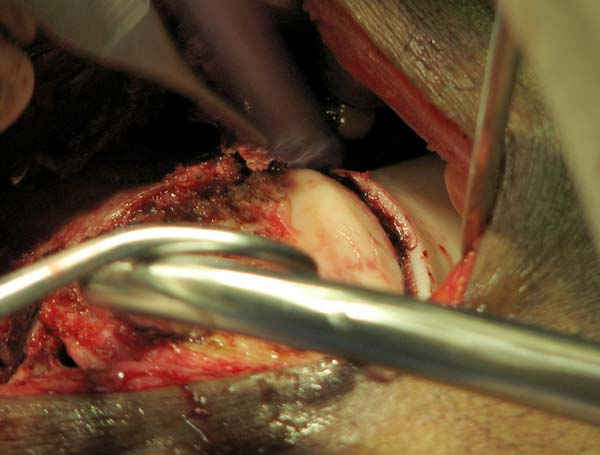

Если идет речь о классификации ран по Gustilo, тогда трудно согласиться с Вашей оценкой, там рана меньше 1 см и подходит больше к первой степени. Такие переломы можно фиксировать любым методом включая пластины и интрамедуллярный способ.

Сустав не дренировался, но медиально перед закрытием раны под фасцией уложен дренаж Hemovac, который удален через 24 часа.

По Густило и Андерсену все high-energy переломы являются III не зависимо от степени повреждения мягких тканей. Plating такого перелома на второй день кажется немного рискованным хотя "победителей не судят". Судя по КТ, медиальный мыщелок стабильный, насколько необходимо было его фиксировать?

Красиво и быстро?! - две пластины + 18 шурупов.

Идеальная репозиция?! -На снимочке A-P проeкции видна "зазубрина" по суставной поверхности, латеральный снимок - тоже не идеально.

Множество мелких FB в кости.